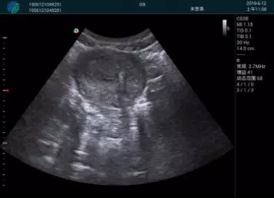

清晰顯示孕囊,通過軟件包計(jì)算孕齡7w+6d

M20實(shí)時(shí)引導(dǎo),術(shù)中清晰顯示孕囊被破壞和抽吸針的過程,清晰顯示吸引針

抽吸結(jié)束后縱切子宮,孕囊已被完全抽吸,未見明顯殘留

橫切子宮,發(fā)現(xiàn)右側(cè)宮腔靠近宮角處有少許脫模樣殘留

M20引導(dǎo)下,抽吸針找到右側(cè)宮角處再次清掃

二次抽吸后再次進(jìn)行超聲檢查,宮腔未見殘留,宮腔線清晰顯示

超聲引導(dǎo)下可視化人流是技術(shù)安全性的保障,一般對(duì)人流術(shù)設(shè)備預(yù)算不高,M20具備婦產(chǎn)科軟件包,且穿透力圖像質(zhì)量好,既滿足人流引導(dǎo)需要,也可用于床旁超聲的需求。